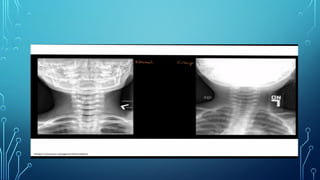

• X-ray Soft tissue Neck lateral- Thumb sign

• Xray neck- AP view – Steeple sign

• Laryngeal examinationis better avoided – red swollen angry epiglottis • X-ray Soft tissue Neck lateral- Thumb sign

• Onset isslow, non toxic • Hoarseness and croupy cough- Barking seal like • Fever low grade • Respiratory difficulties is slow in onset with intercostal and suprasternal recession • Xray neck- AP view – Steeple sign